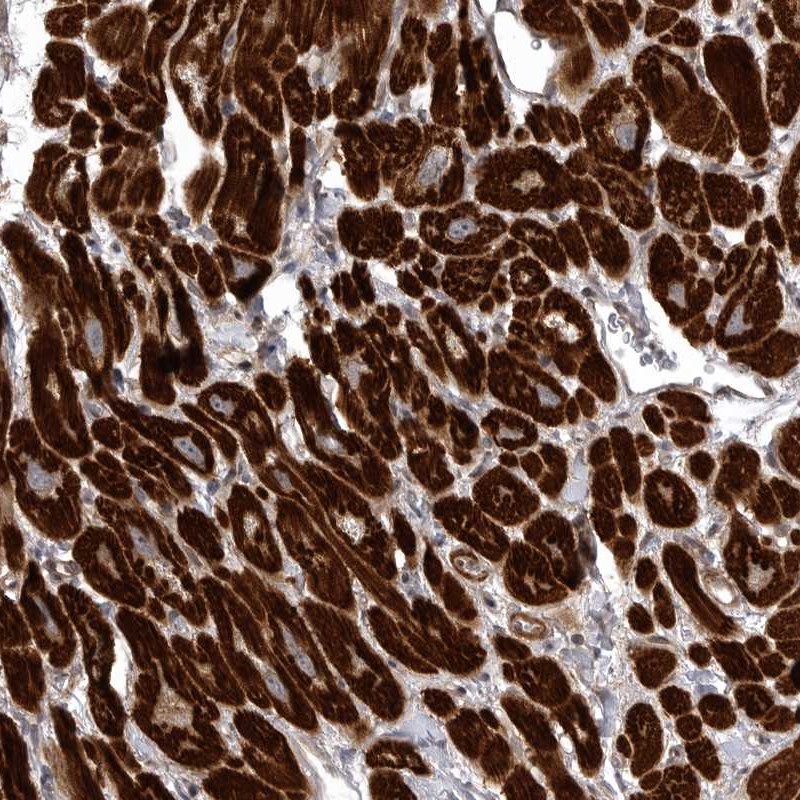

Immunohistochemical staining of human heart muscle shows strong cytoplasmic positivity in myocytes.